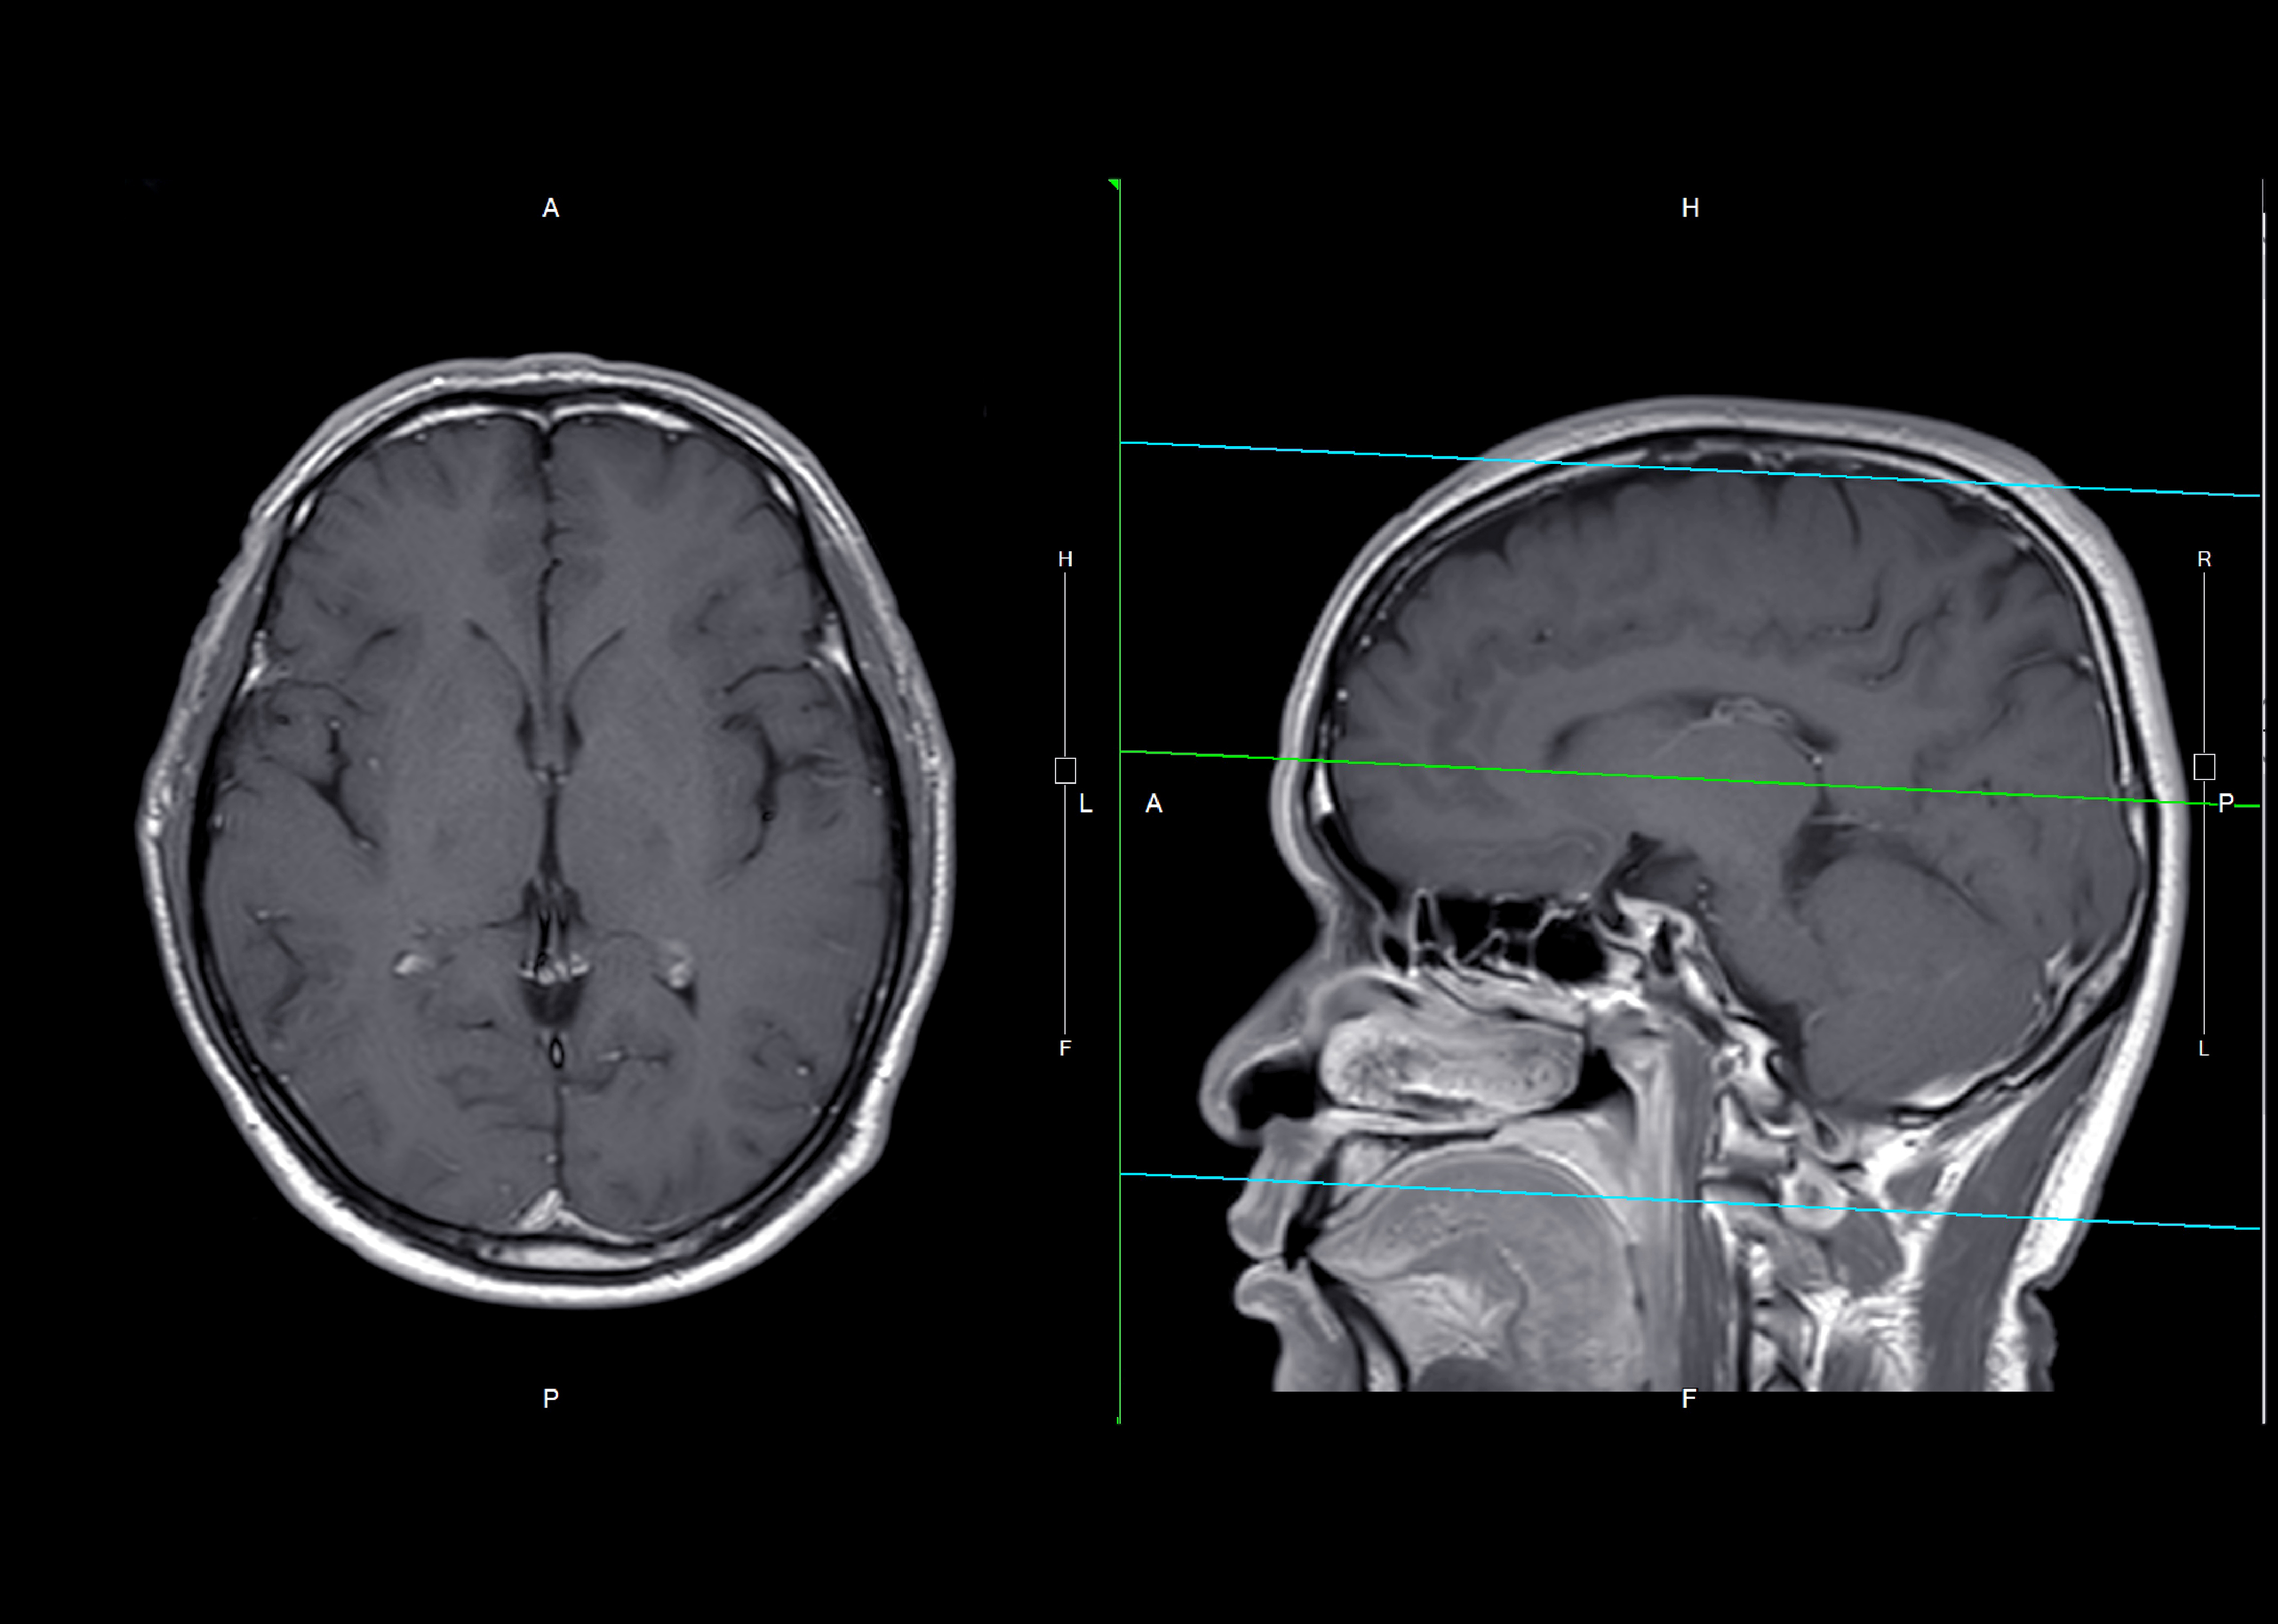

(Image: Brain MRI using gadolinium contrast agent by Suphachai Praserdumrongchai via Getty Images)